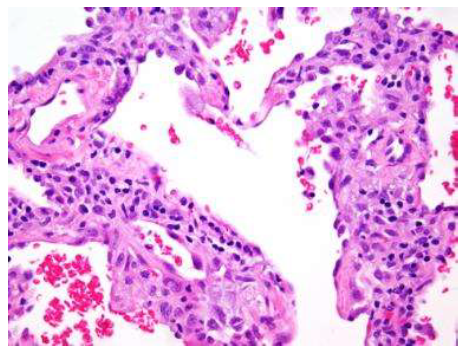

מה הממצא

פניאומוניה ויראלית

רואים פילטרט של לימפוציטים באינטראסצטיום ללא אקסודאט באלבאולות

מאפיינים היסטולוגים של פניאומוניה ויראלית

דפנות אלבאולריות מעובות

חללים אלבאולרים ריקים